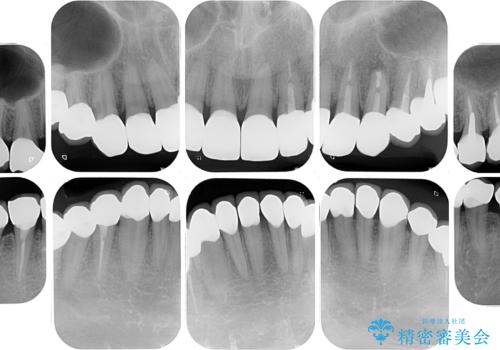

- すぐに欠けてしまう前歯や、むし歯で全顎的に処置された歯を気にして来院された患者様です。

元来むし歯が多く、さらに受け口傾向の咬み合わせを気にしていらっしゃいました。

当初はむし歯処置が必要な歯のみの治療予定でしたが、捻転や咬み合わせを可及的に改善したいとのことで、全顎的にオールセラミッククラウンにて補綴治療を行うこととしました。